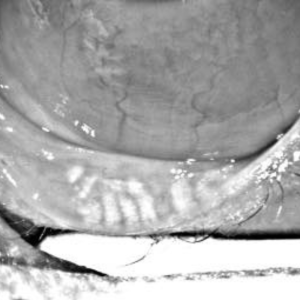

Healthy Meibomian Glands vs Gland Loss

As gland structure changes over time, the eye becomes less able to maintain a stable tear film. Early treatment focuses on preserving gland function and improving how the remaining glands work.